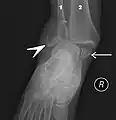

Fracture bimalléolaire de la cheville.